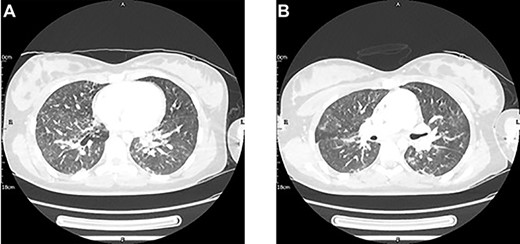

On Day 3, she underwent surgical fixation of her fractured femur. Pre-operative complications included desaturation events en route to, and within, the anaesthetics room. Here, axillary petechiae were noted and fat globules were visible within an arterial blood sample (ABG, Fig. 2). A diagnosis of FES was made, and the anaesthetic and surgical plan subsequently adjusted to preclude clinical deterioration. A femoral but not a sciatic nerve block was sited in order to avoid moving the affected limb. The femur was fixed with a plate, chosen to avoid exacerbating the release of fat emboli, in contrast to an intramedullary nail [5].

Imaging can be a helpful adjunct to clinical assessment of FES. Thoracic CT has shown diagnostic potential, with patchy ground-glass opacities with areas of sparing plus smooth interlobular septal thickening a consistent radiological features in FES [1, 2]. However, an initial negative CT does not rule out FES, and one must consider the consequences of repeated radiological exposure in a young female patient such as ours [2]. In addition, specificity is currently hindered by COVID-19. More promising is cerebral MRI, with the presence of dispersed hyperintense lesions on T2-weighted images found to be sensitive for FES in patients with cerebral involvement, even in those with a normal CT like our patient [2, 5, 6]. Cerebral involvement is not reliant on paradoxical emboli, and radiological signs can appear as early as 4 h post trigger [2, 5–7].